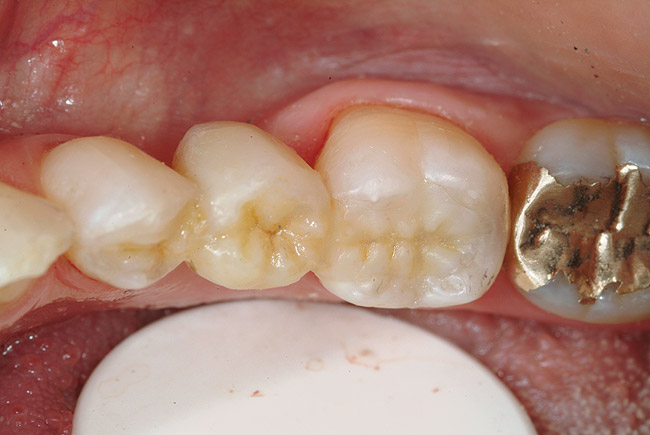

Figure 6a  Missing mandibular premolar; the patient has declined the placement and restoration of missing tooth with an implant. The clinical decision was for a fiber FPD.

Figure 6a